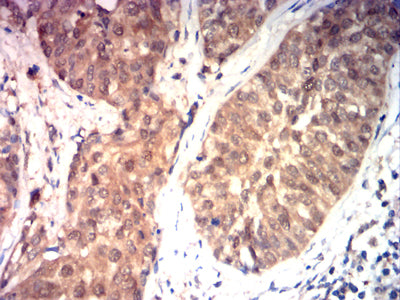

Immunohistochemical analysis of paraffin-embedded human bladder cancer tissues using HSP70 mouse mAb with DAB staining.

Immunohistochemical analysis of paraffin-embedded human rectal cancer tissues using HSP70 mouse mAb with DAB staining.